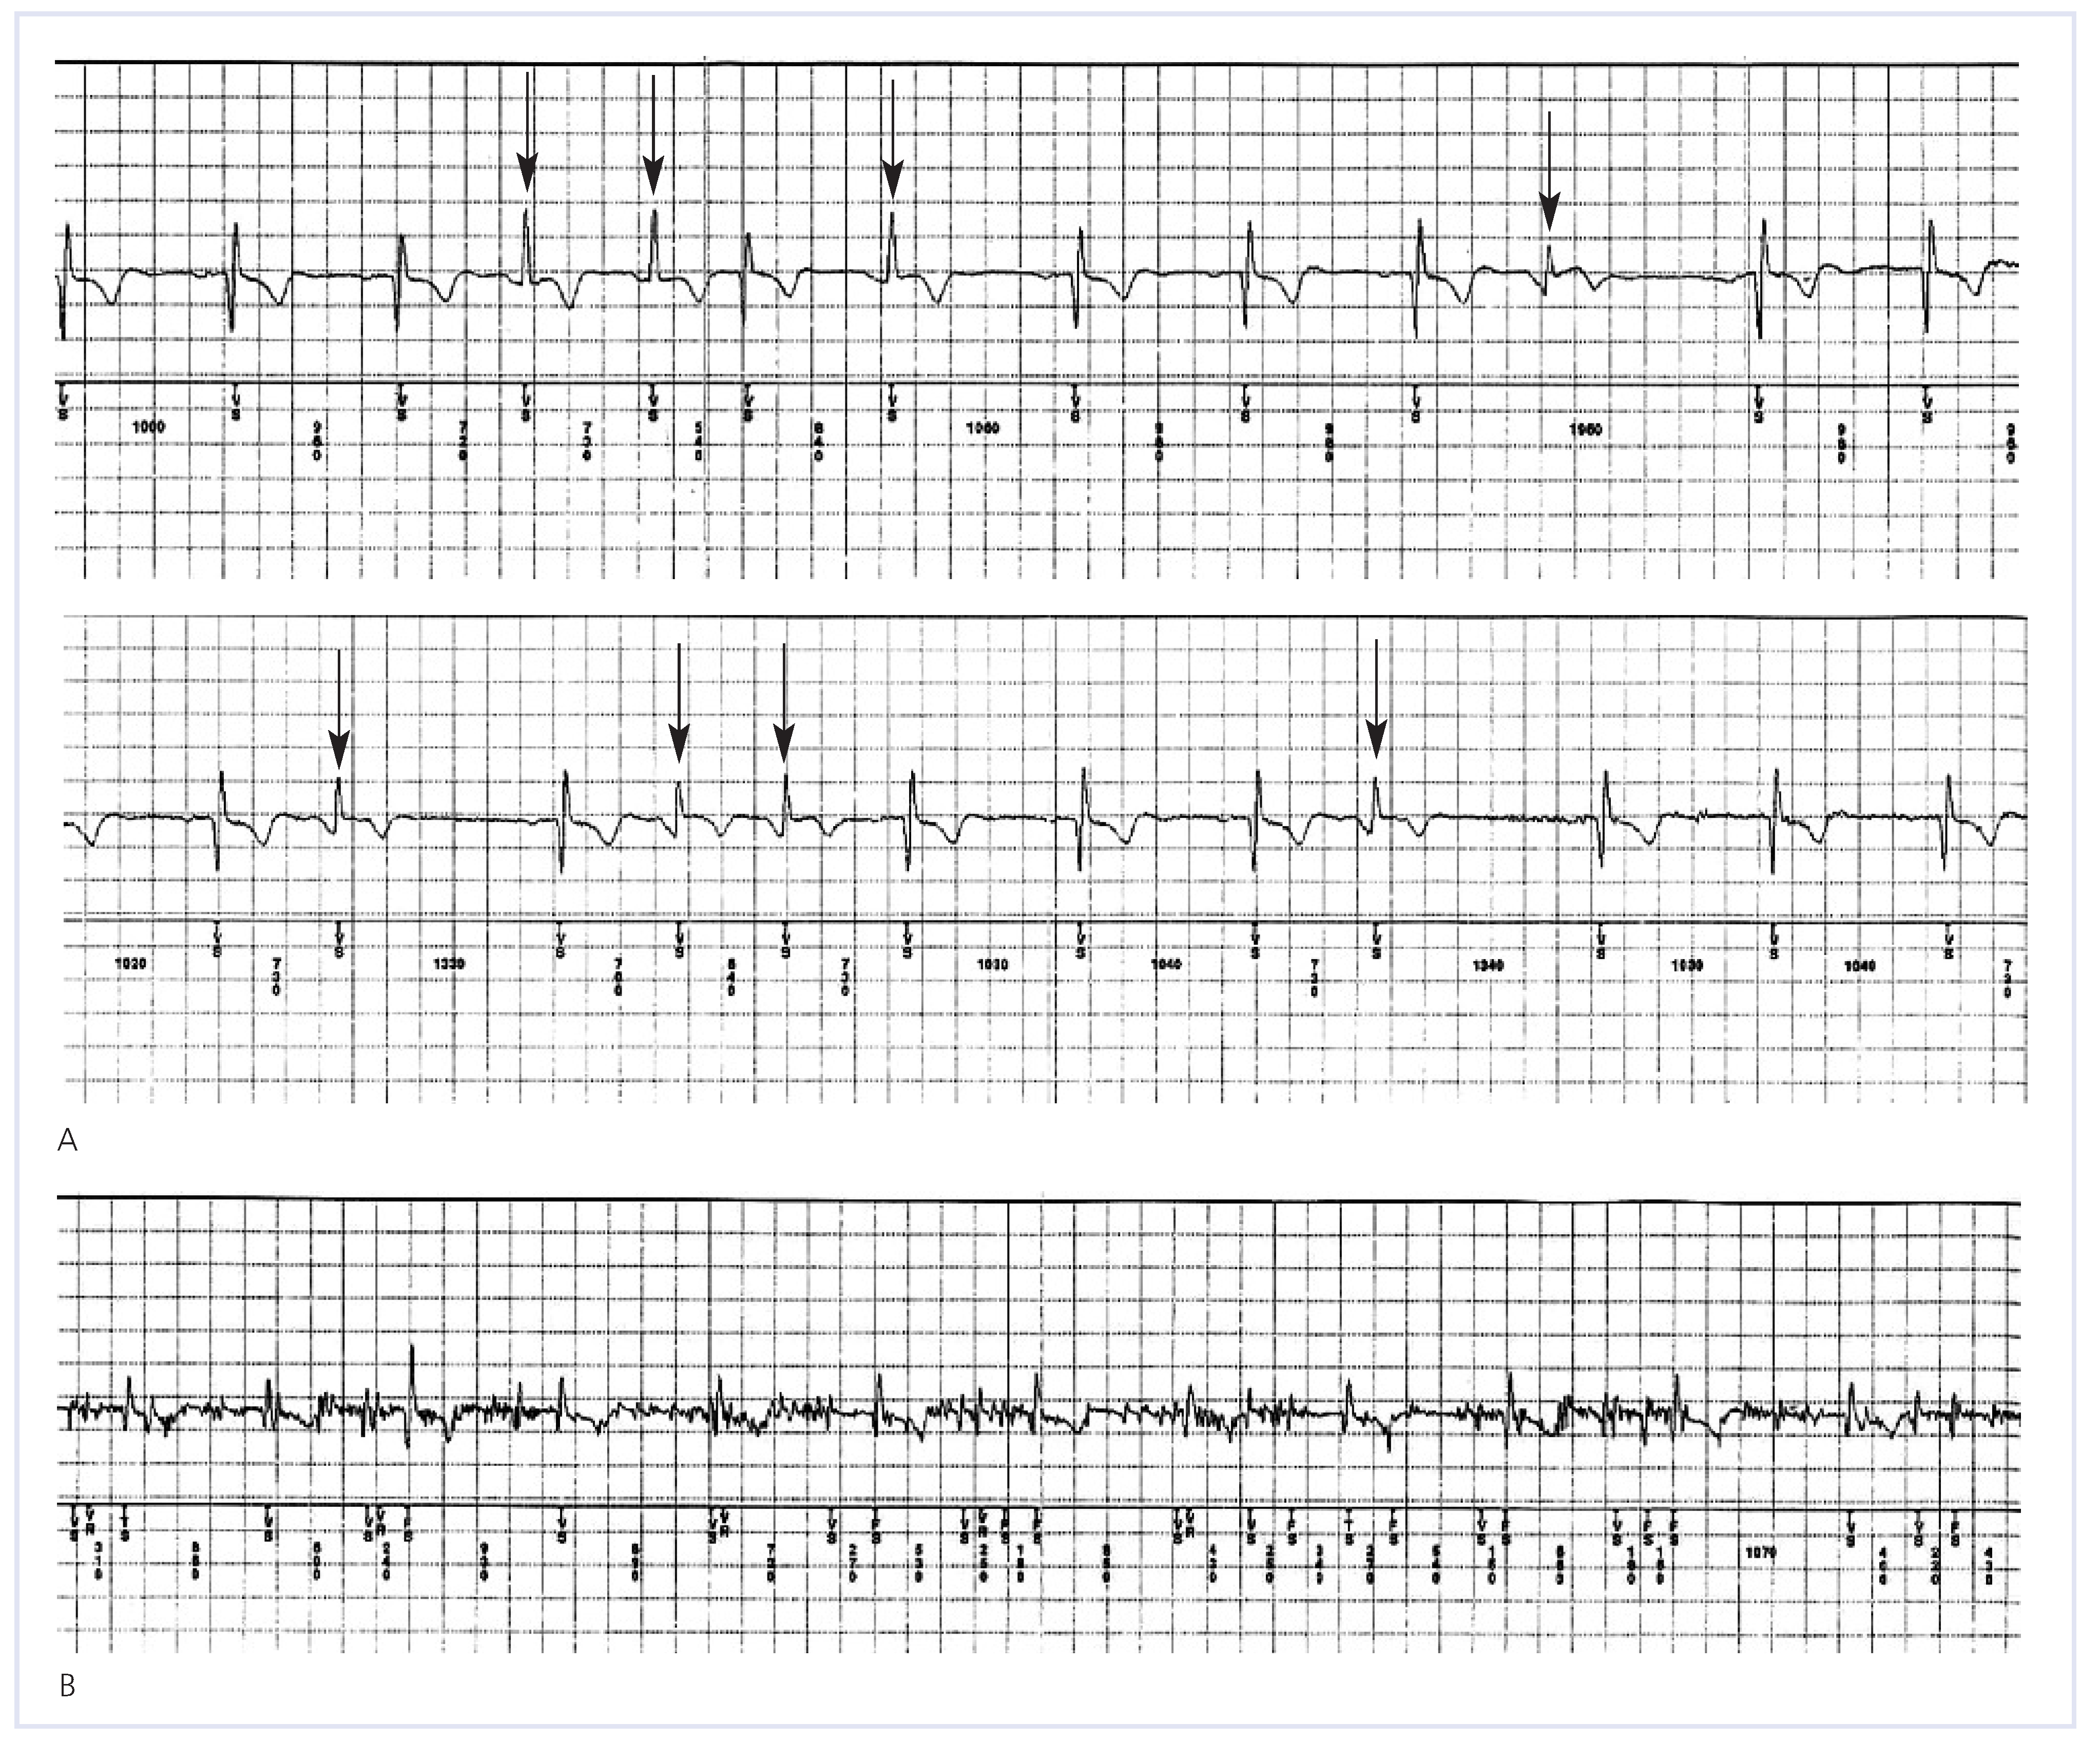

Figure 2.

Examples of appropriate detection by the ILR. (A) shows an example of a patient-activated recording following a near syncopal event. A narrow complex tachycardia at a rate of 167 bpm is triggered by a ventricular couplet (arrows). An electrophysiological study diagnosed runs of atrioventricular nodal tachycardia. (B) shows an example of supraventricular tachycardia automatically recorded by the ILR during a syncopal event. The overt variability of R-R intervals and the absence of QRS morphology changes (not shown) were diagnostic of paroxysmal atrial fibrillation. Normal sinus rhythm is shown in another example in (C), followed by a 5-sec duration sinus arrest and syncope. The patient was successfully implanted with a double-chamber pacemaker. (D) shows a syncopal sudden change in morphology and rate (240 bpm) during exercise that happened to be a sustained ventricular tachycardia in a patient with hypertrophic cardiomyopathy and unexplained syncope.